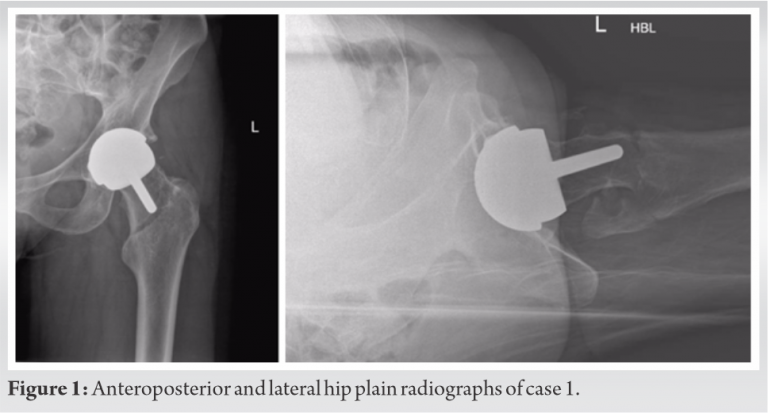

The three cases that we describe in this paper are homogenous in presentation, treatment and outcome, and therefore presented in the table below (Table 2). Pre-operative (Fig. 1-3) and post-operative (Fig. 4-6) radiographs are also included for each of the cases. 3-D reconstructed images from a computerized tomography (CT) scan for case 3 can be visualized as part of (Fig. 3).

All patients were independently mobile, active with well-fixed and well-functioning RHAs before the date of injury. All patients suffered low-energy trauma causing the fracture. All patients underwent CT scans to further delineate the fracture pattern, to assess for radiographic signs of loosening, and to assess bone stock and suitability for fixation. Intraoperatively, patients were placed on a traction table. Optimal closed reduction of the fracture was achieved using intraoperative image intensifier (II). An extended direct lateral approach to the proximal femur was used. The fascia lata was divided along its fibers and the vastus lateralis split. Fracture reduction was improved, held with 2 mm Kirschner wires placed across the fracture site, and position confirmed with II. An anatomically contoured distal femoral variable angle LCP (VA-LCP) intended for the contralateral distal femur was measured, selected, and positioned in an inverted manner (proximal and distal ends reversed). The position was checked using image intensifier. A non-locking fully threaded cortical screw was inserted distal to the fracture site to seat the plate to bone. The senior author believes that it is essential to achieve the best possible screw hold in the neck, and therefore accept to some extent that the plate distally may not sit perfectly centered over the shaft of the femur. Shaft screws can be inserted distally through a minimally invasive plate osteosynthesis technique if desired. All patients were asked to partially bear weight on the operated side for 8 weeks. The time to radiographic union and the time to discharge from physiotherapy with achievement of previous level of function were recorded for two patients. One patient, case 3 (Fig. 3, 6), was lost to follow-up as she moved out of the country.